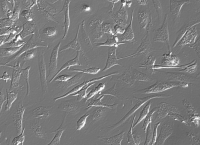

中文名称:人非小细胞肺癌细胞

形态:上皮细胞样

背景资料:这株细胞来源于一个淋巴结转移。患者接受了初期放疗。细胞均一性的部分缺失p53蛋白,并缺少p53蛋白表达。细胞可以合成0.1pmol/毫克蛋白的NMB蛋白,而不合成促胃液释放肽(GRP)。